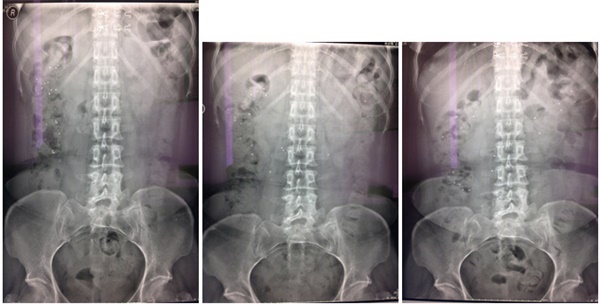

2、结肠传输试验

结肠传输试验是检查人体结肠传输功能的一种方法。通过口服不透X光标记物,使其混合于肠内容物中,在比较接近生理条件的前提下,分别于口服标记物后24小时、48小时及72小时摄片,观察结肠的运动情况.

3、下消化道造影:下消化道造影,是了解结肠器质状态的较好方法之一。

结肠传输试验阳性 (考虑出口梗阻型)